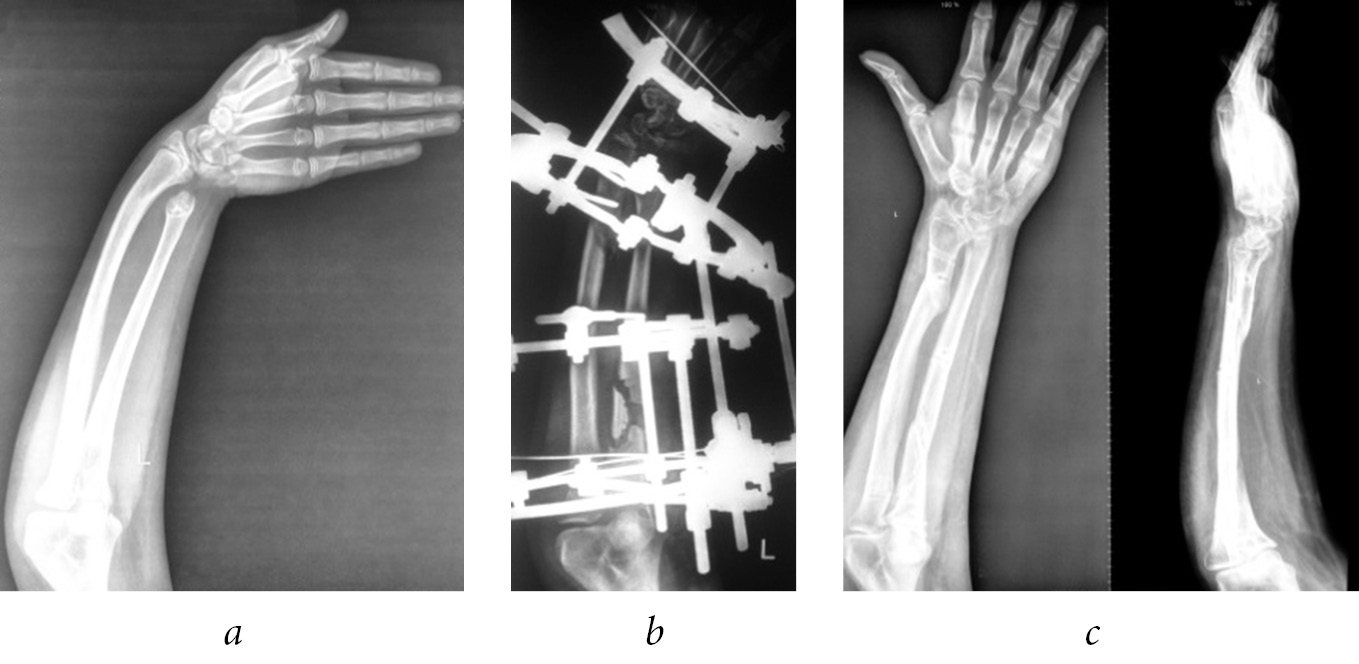

Having studied the orthopedic problems of patients with a history of meningococcal sepsis, Park and Bradish [17] concluded that elongation of the bones of the forearm should be performed when it is shortened by more than 5 cm. The authors also believed that when shortening one of the bones of the forearm, which causes the formation of the same clubhand, the deformity should be elongated and corrected only on the shortened and deformed bones. And upon reaching the correction of deformity, it is recommended to perform epiphysiodesis on both bones to prevent recurrence of deformity. At the same time, they admit that epiphyseodesis can lead to a significant shortening of the forearm and the need for repeated elongation.

We believe that elimination of deformity of only a shortened bone is not enough, since in the process of child growth, the adjacent forearm bone is deformed, causing pronounced cosmetic and functional disorders (Fig. 5).

Fig. 5. Radiographs of the left forearm of patient G. before (a), in the process (b), and after (c) the elimination of the ulnar clubhand